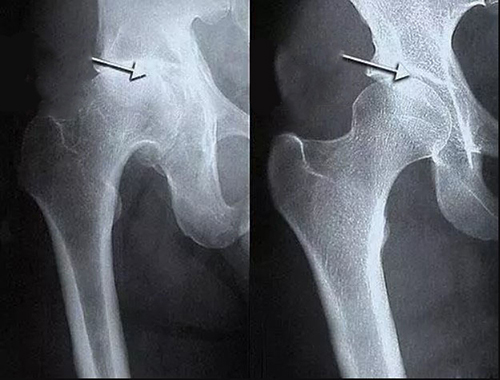

นี่เป็นเพียงรายชื่อโรคอย่างย่อเท่านั้น โรคอื่น ๆ ล้วนเป็นเพียงกลุ่มย่อยของพยาธิสภาพหลักทั้ง 9 ประเภท เช่น โรคข้อสะโพกเสื่อม (Coxarthrosis) ก็เป็นชนิดหนึ่งของโรคข้อเสื่อม (Osteoarthritis) เป็นต้น

และโรคทั้งหมดเหล่านี้สามารถรักษาได้ด้วยการล้างข้ออย่างง่ายและมีประสิทธิภาพ วิธีนี้ปลอดภัยอย่างสมบูรณ์ และสามารถทำได้ง่ายที่บ้าน